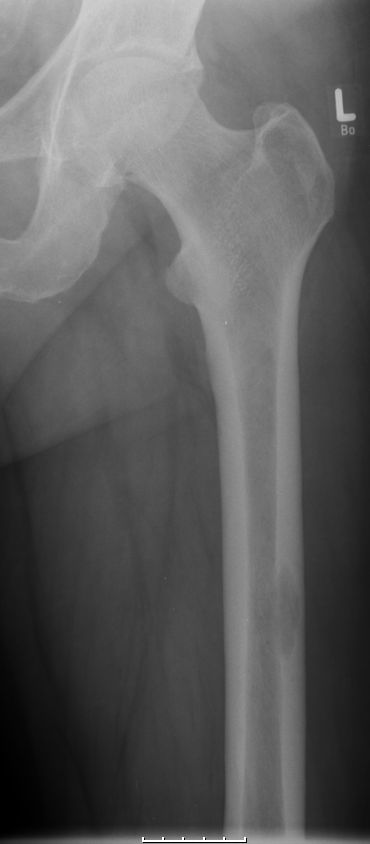

Femurschaftmetastase![]() | ||